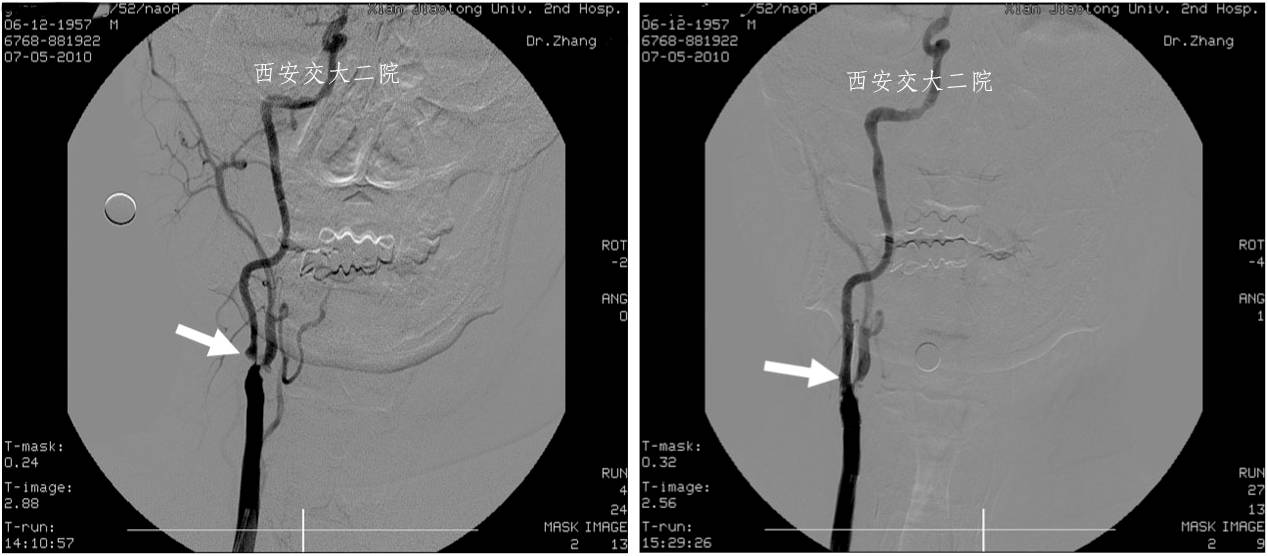

Case 2 颈内动脉眼动脉段狭窄(2010年)

》女,51岁,左侧肢体无力1月,加重20天,DSA示右侧颈内动脉眼动脉段狭窄80%。